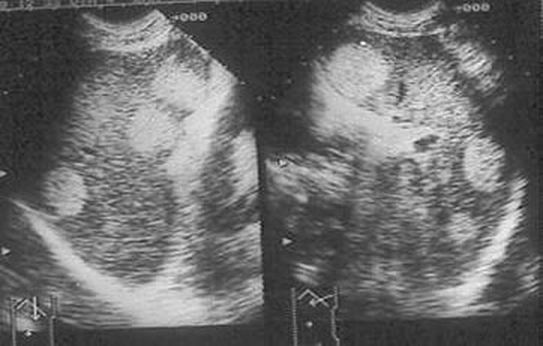

El linfoma es la causa más frecuente de lesión ocupante de espacio esplénica. La afectación esplénica por el linfoma puede ser focal o difusa. Si la infiltración es focal en la ecografía se observarán lesiones nodulares de diferentes tamaños, generalmente hipoecogénicas. Cuando la infiltración esplénica por el linfoma es difusa, la ecografía sólo detectará una esplenomegalia con ecogenicidad más o menos homogénea. Este hallazgo puede ser totalmente inespecífico ya que en algunos casos de linfoma, la esplenomegalia puede ser debida a otras causas.